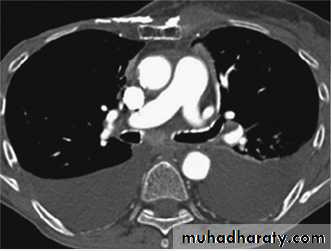

Radiology

Chest X-RayUltrasound (US) is able to demonstrate small effusions.

Computed tomography (CT).

Chest X ray: The pleural fluid accumulates in the most dependent part of the thoracic cavity

The normally sharp posterior costophrenic angle is obliterated.

Upper surface is meniscus-shaped (meniscus sign).

Around 200 mL of fluid is required in order for it to be detectable

on a PA chest X-ray

The amount of pleural effusion may be small, large or massive.

Plueral malignancyPrimary: Mesothelioma is a malignant tumour affecting the pleura (pleural mesothelioma) or, less commonly, the peritoneum (peritoneal mesothelioma) due to asbestos exposure. It has poor prognosis.

Malignant mesothelioma

Small pleural effusions can be detected best by ultrasound (or CT).The most important laboratory parameter of pleural fluid is total protein, distinguishing trans- and exudates.